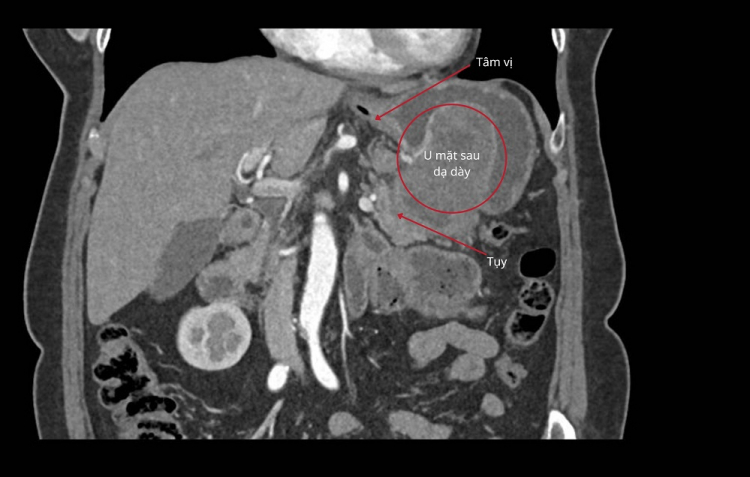

Khối u GIST dính vào tụy và mặt sau dạ dày gần tâm vị

Theo ThS.BS CKII Phan Văn Thái - Trưởng khoa Ngoại Tổng quát (Bệnh viện FV), khối u mô đệm (GIST) của bệnh nhân H.T có kích thước khoảng 5x5x7cm. Tuy nhiên, điều đáng lo ngại là ở vị trí và cấu trúc phức tạp của nó: khối u nằm khuất ở mặt sau dạ dày, sát tâm vị, dính vào bề mặt tụy và đã hoại tử khoảng 30% - những yếu tố khiến việc can thiệp trở nên đặc biệt thách thức.